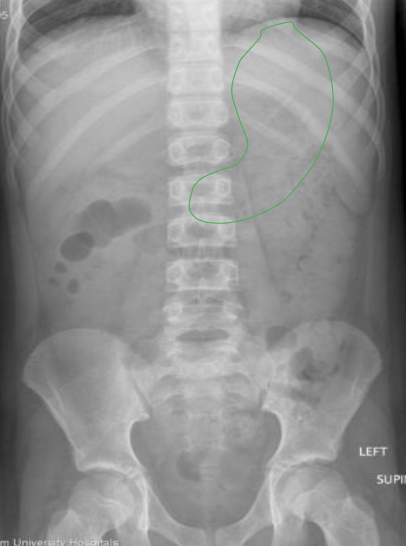

What anatomy is outlined in this image?

Stomach